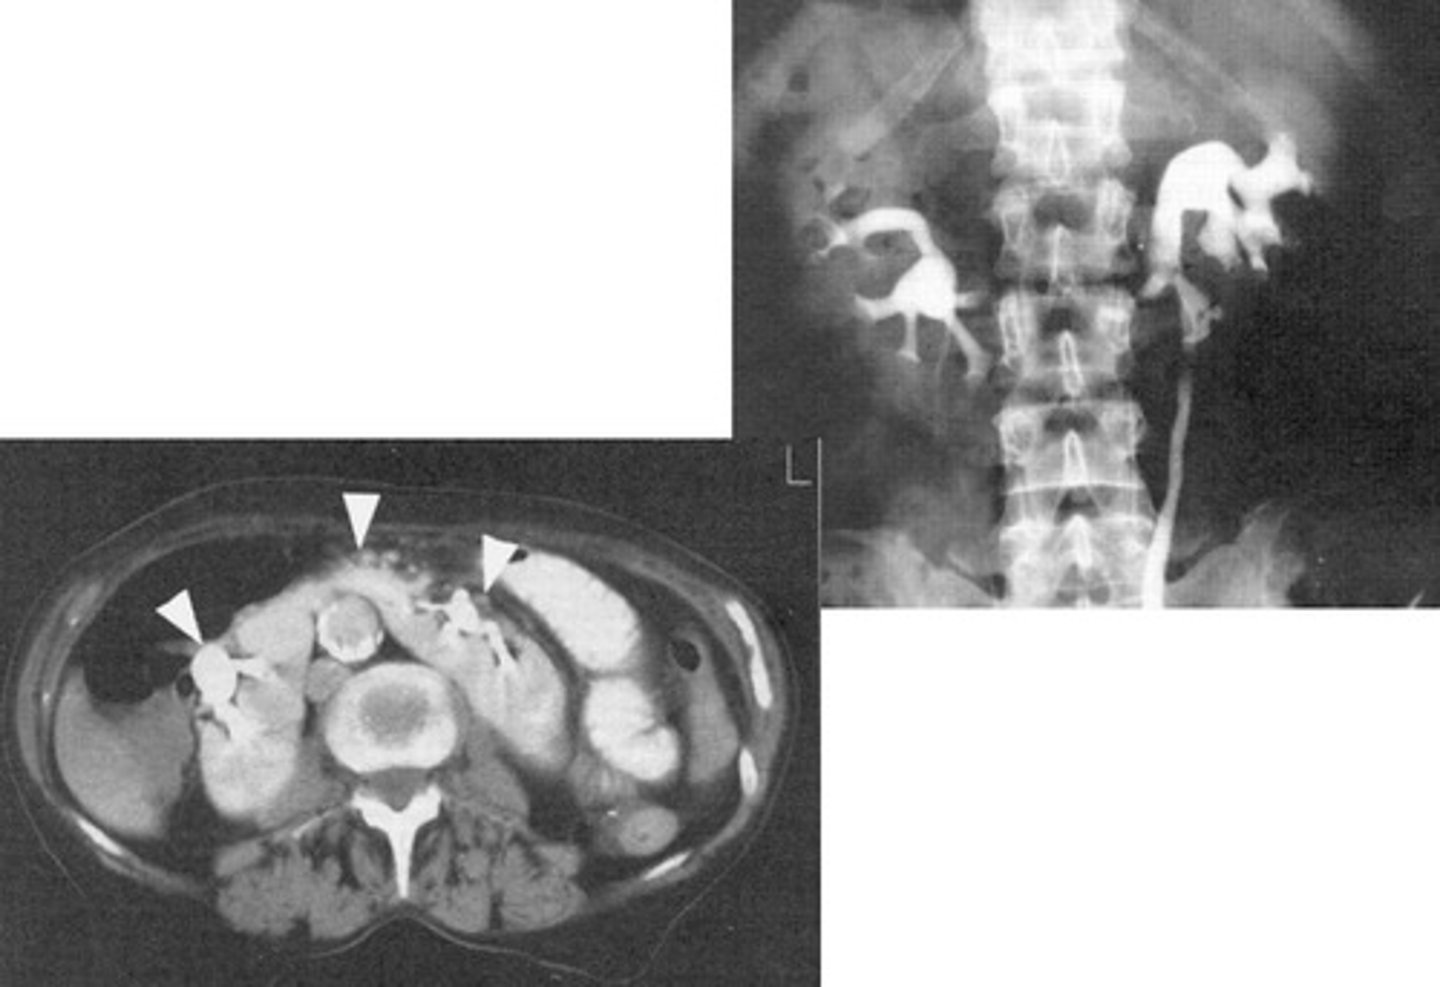

- Urinary Tract Obstruction

- Hydroureter and hydronephrosis

- CT, U/S, delayed IVU

- What pathology is caused by a stone, tumor, stricture, enlarged prostate, congenital anomaly, or pregnancy?

- What can happen to the ureters and kidneys?

- What imaging modalities are used to see this pathology?

Hydronephrosis

What is the condition where one or both kidneys become stretched and swollen as the result of a build-up of urine inside them?